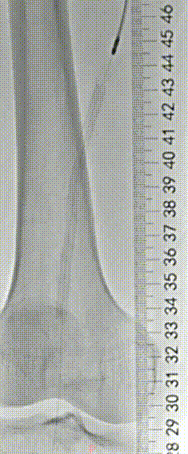

▲术前血管造影与CTA相符

▲采用导丝通过支架内闭塞段顺利,考虑为内膜增生合并部分陈旧性血栓病变,再次造影明确病变长度。

▲血管斑块旋切系统逐段旋切抽吸病变段。

▲造影提示治疗效果良好,成功开通闭塞段。

▲Blades Up模式再次抽吸病变段,股腘动脉管腔获得满意,膝下胫后动脉、足部血流灌注同前,未见明显栓塞。

▲股浅、腘、胫后动脉经POBA+5*300 先瑞达DCB球囊扩张。

▲治疗完毕,最终造影结果,股浅动脉局部非限流性夹层,支架内、膝下流出道血流速满意。